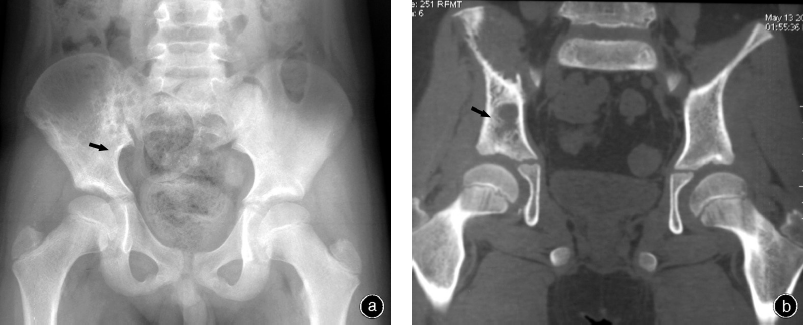

2001年1月至2010年10月,采用经“Y”型软骨 截骨、髋臼部分切除治疗8例骨盆尤文肉瘤患者,男6例,女2例;手术时年龄7~16岁,平均12.7岁。依据肌肉骨骼肿瘤协会(MSTS)分型:8例均为TypeⅡ型(累及髋臼),其中3例位于“Y”型软骨上方(我们命名为TypeⅡA型),4例位于“Y”型软骨前下方(我们命名为TypeⅡB型),1例位于“Y”型软骨后下方(我们命名为TypeⅡC型,图1)。依据X线片、MRI、CT、骨扫描、胸部CT等对肿瘤进行分期,本组患者骨盆肿瘤均为局部肿瘤,未发生远处转移。所有手术均由同一组骨肿瘤医生完成。本研究均经本院伦理委员会批准,患者均知情同意。

本组患者均获得随访,随访时间为12~72个月,中位随访时间为37.8个月。其中7例患者无瘤生存时间为24~60个月,平均39个月(图3,4);1例患者因肺部转移而于术后24个月死于呼吸、循环衰竭。本组患者两年生存率为100%,五年生存率为 87.5%(7/8)。